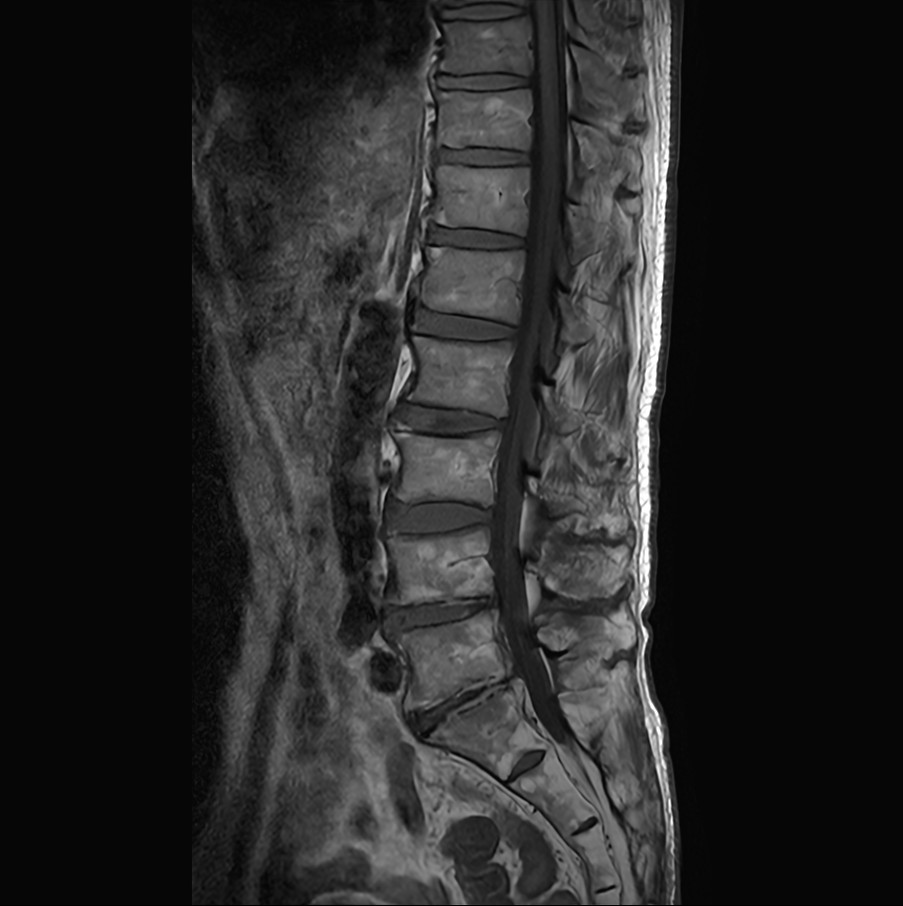

Lumbar Spine fracture with SmartSpeed Precise

Sagittal T2w TSE